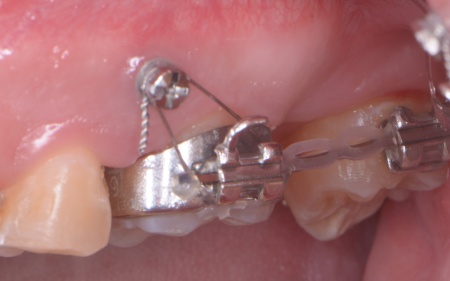

続いて歯茎に矯正用インプラントと呼ばれるネジを打ち込み、これと隣の歯を固定源としながら、埋まっている親知らずを矯正の力で引っ張りだしました。

矯正治療により、親知らずが歯並びのラインに収まってきたところで、歯根の先端を手前側に起こす力を与えるためにワイヤーをかけ、歯を移動させながら歯列が平行になるように調整します。